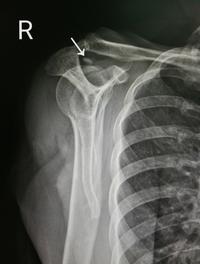

La tendinopathie calcifiante de l’épaule est l’une des causes les plus fréquentes de douleurs non traumatiques de l’épaule, caractérisée [...]